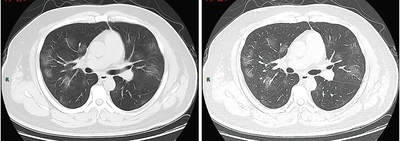

الأشعة المقطعية

Chest CT scans can sometimes help identify and characterize lung pathology, and have yielded non-specific findings with COVID-19 infection. A systematic review of chest CT scan findings in 919 patients described the typical early manifestation of COVID-19 as "bilateral multilobar ground-glass opacification (GGO) with a peripheral or posterior distribution".[133] One study found that the sensitivity of CT for COVID-19 infection was 98% compared to RT-PCR sensitivity of 71%; however, this was performed in Wuhan province of China and is not generalizable.[134] Most common CT scan findings were bilateral ground-glass attenuation (patchy or diffuse) with subpleural dominance, crazy paving and consolidations at later stages.[135] These findings are nonspecific and found as well in other types of pneumonia. A small study showed that Chinese radiologists demonstrated 72-94% sensitivity and 24-94% in differentiating COVID-19 from other types of viral pneumonia using CT imaging.[136] No study yet has validated the accuracy and discriminatory value of CT scans to distinguish COVID from other viral pneumonia. Therefore, the CDC does not recommend CT for initial screening, as emphasized in the COCA call on Thursday, 5 March. People with suspected COVID should be tested with RT-PCR, which is the most specific test.[بحاجة لمصدر]